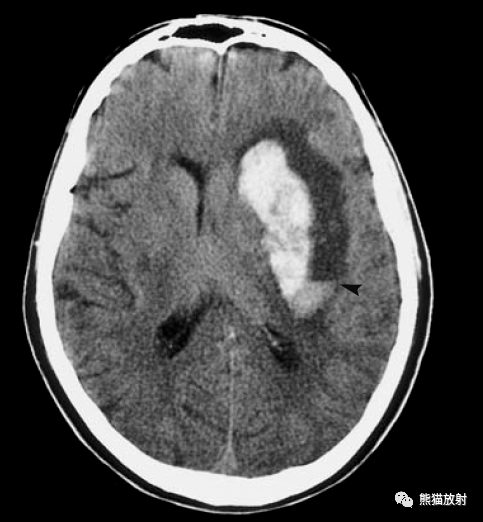

内囊出血

快速识别脑出血部位

不同部位脑出血的表现

精心整理快速学会脑出血部位辨识

患者:刘洪波,男,50岁,右侧基底节区脑出血

脑实质内出血丨演变分布ct表现